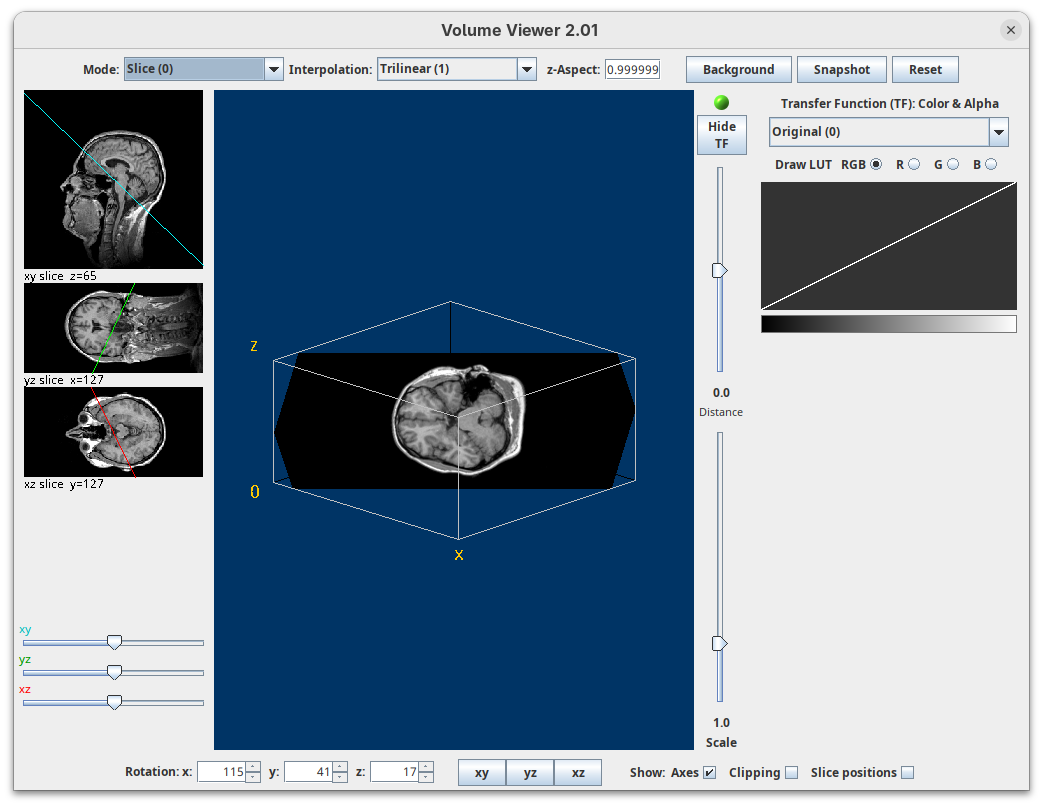

Volume Viewer

Volume Viewer is a more powerful plugin for 3D visualization as it supports slicing, projections, and rendering. The interface is interactive and intuitive to use. To open it:

- Go to

Plugins>Volume Viewer. The main interface will open in theSlicemode.

- Click around and move the sample to see optical sections from different angles.

- Then, activate the

Volumemode to render the sample’s surface in 3D and explore it as well, playing with the different rendering parameters.

Volume Viewer also provides a way to take snapshots of the current view.